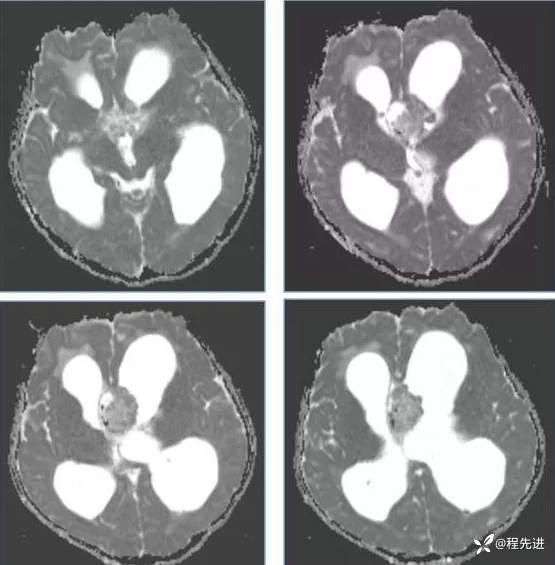

【神经】特别精彩病例|行走不稳2月余

患者性别:男

患者年龄:13岁

主诉:行走不稳2月余

现病史:2个月前患者无明显诱因下出现行走不稳,近期症状逐渐加重,站立不能。病程中患者无意识障碍,无头痛头晕,无明显恶心呕吐、视物旋转、耳鸣、眼球活动障碍等,无尿量增多、泌乳、口干等,体重无明显改变,睡眠可,食欲可,二便正常。

既往史:患者生后8个月和今年出现两次癫痫发作,持续时间不长

个人史:患者自幼失语,智力障碍

专科检查:右侧肢体肌力III-IV级,左侧肢体肌力IV级,肌张力下降